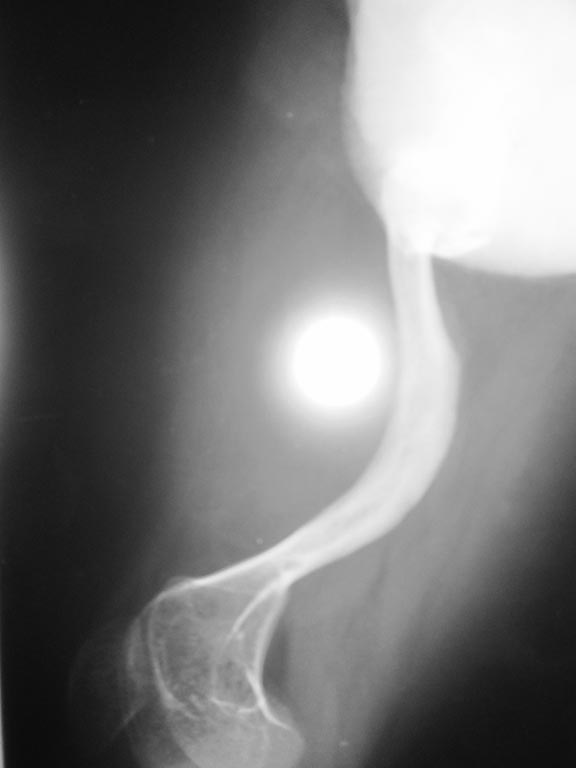

На Рентгенограмме левого бедра: Ложный сустав нижней трети бедренной

кости слева, грубая многоплоскостная деформация бедренной кости.